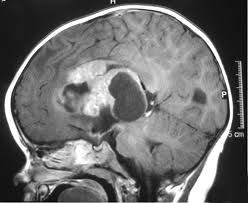

What Causes Brain Cancer In A Child / Brain Cancer Overview And More - Some kids who have certain genetic conditions have a greater chance of developing brain tumors.. These abnormalities are caused by alterations directly in the genes, or by chromosome rearrangements that change the function of a gene. And they vary between children. The majority of brain tumors have abnormalities of genes involved in cell cycle control, causing uncontrolled cell growth. As they get bigger, these tumors can press on the cells around them and cause damage. A brain tumor is a mass that grows in your child's brain, or in an area near the brain.

Tests that examine the brain and spinal cord are used to detect (find) childhood brain and spinal cord tumors. They can also indirectly damage cells by pushing on other parts of the brain. Brain and spinal cord tumors in children are the result of cells growing out of control. Many studies have sought to identify the causes of childhood cancer, but very few cancers in children are caused by environmental exposure or lifestyle factors. Chemotherapy side effects depend on the type and dose of.

Cancer from www.who.int These abnormalities are caused by alterations directly in the genes, or by chromosome rearrangements that change the function of a gene. Brain tumors and other nervous system tumors make up about 27 percent of childhood cancers. Many tumors are more common at a certain age. Doctors classify brain and central nervous system tumors based on where they form and the kind of cells they involve. Chemotherapy uses drugs to kill tumor cells. However, factors that can increase your risk of brain cancer include exposure to high doses of ionizing. Most exposures that cause cancer, such as tobacco smoke, somehow damage dna. Brain tumors are the most common solid tumors affecting children and adolescents, with close to 5,000 children diagnosed each year.;

Astrocytomas are tumors that start in certain brain cells called astrocytes, which are a type of glial cell. This is different to cancers that have spread to the brain from somewhere else in the body. More children than ever are surviving childhood cancer. Childhood astrocytoma is a form of brain cancer in which cells in the brain start to grow abnormally. Astrocytoma is the most common type of glioma diagnosed in children. Learn about the causes, symptoms, and treatment of ependymomas, a type of spine and brain cancer that affects children and adults. Causes and risk factors for brain cancer the exact cause of brain cancer is unknown. Boys are affected slightly more often than girls. The majority of brain tumors have abnormalities of genes involved in cell cycle control, causing uncontrolled cell growth. A brain tumour is a collection of cells that have grown in an uncontrolled way. Although the drugs can be taken orally in pill form, in children with pediatric brain tumors the drugs are usually injected into a vein (intravenous chemotherapy). Examples include nerves in your child's skull, his pituitary gland, or the membranes that cover his brain. The cause of most childhood brain and spinal cord tumors is unknown.

See your gp if your child has any symptoms of a brain tumour to get them checked over. Many children with a brain tumor experience headaches before their diagnosis. Most brain tumors in children start in the lower parts of the brain, such as the cerebellum or brain stem. When a child develops a brain tumor, early diagnosis is essential. Brain tumors can directly destroy brain cells.